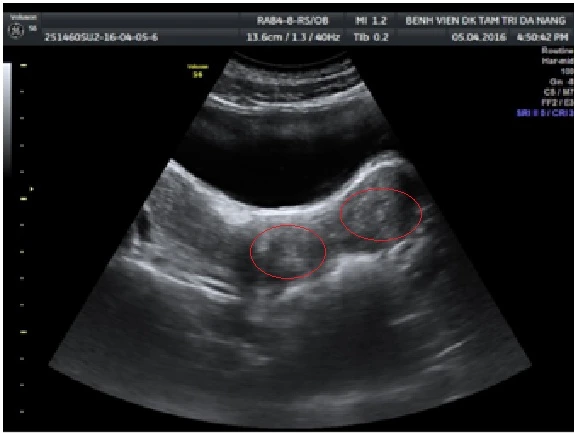

Sau khi được nhập viện, bé được thông tiểu. Kiểm tra qua đường trực tràng có khối căng to đè vào trực tràng và kết quả siêu âm thấy khối tụ máu lớn 140x60 mm, lan từ tử cung đến âm đạo, buồng trứng.

Hình ảnh siêu âm cho thấy hai tử cung đều dị dạng. (Ảnh do bệnh viện cung cấp)

Sau tiến hành phẫu thuật, kiểm tra siêu âm lại các bác sĩ kết luận bé gái bị dị dạng hai tử cung, hai âm đạo nhưng có một âm đạo không thông với màng trinh dẫn đến việc ứ máu khi đến tháng, gây đau cũng như chèn ép gây bí tiểu và táo bón. Bên cạnh là dị dạng tiết niệu với một quả thận duy nhất.